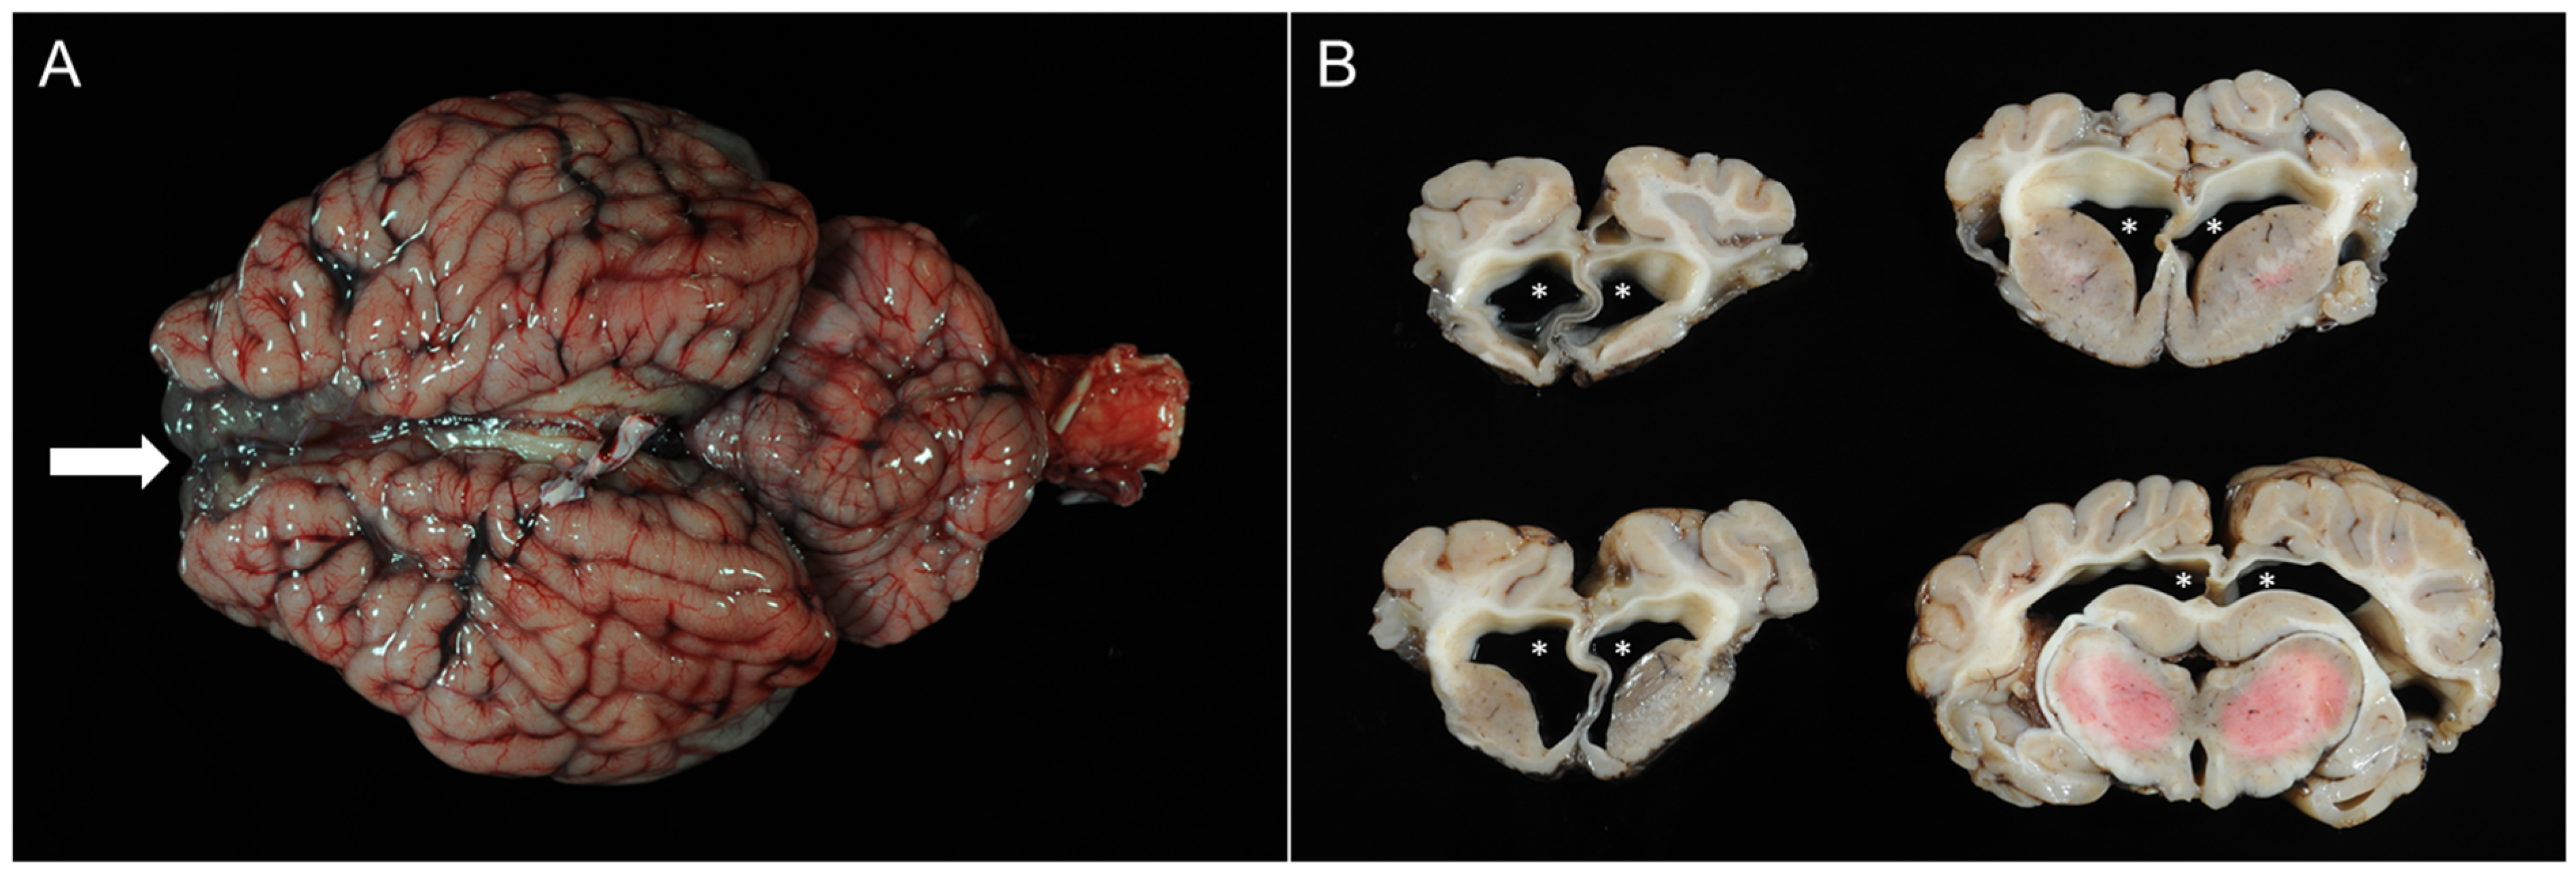

3.4. Pathomorphological Findings

3.4.1. Case 1

3.4.2. Case 2